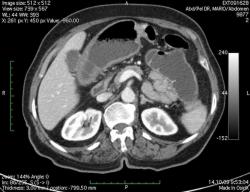

КТ брюшной полости. Женщина 73 года с жалобами на запоры.

Пациентка женщина 73 года. Предъявляет жалобы на запоры, спастические боли в брюшной полости.

ИзображениеЦиркулярное сужение в поперечной ободочной кишке. Ни это ли причина проблемм?

Новообразование в среднем отделе поперечной ободочной кишки с циркулярным сужением просвета и хронической механической толстокишечной непроходимостью. Признаков метастазирования в данной анатомической области не обнаружено. Пациент безусловно нуждается в хирургическом лечении.

Я не занимаюсь КТ, но сам характер сужения толстой кишки как-то вызывает сомнения, ракового ли он характера? Сужение то циркулярное, но больно уж ровненькое и нет признаков инфильтрации вокруг (хотя рак, конечно может иметь и такой вид). Ну, думаю dr.Mario со временем откроет карты и будет дана гистология.

Циркулярная стенозирующая опухоль (аденокарцнома) толстого кишечника; с типичной КТ презентацией и признаками обструкции. Пациентка была оперирована на второй день после КТ.